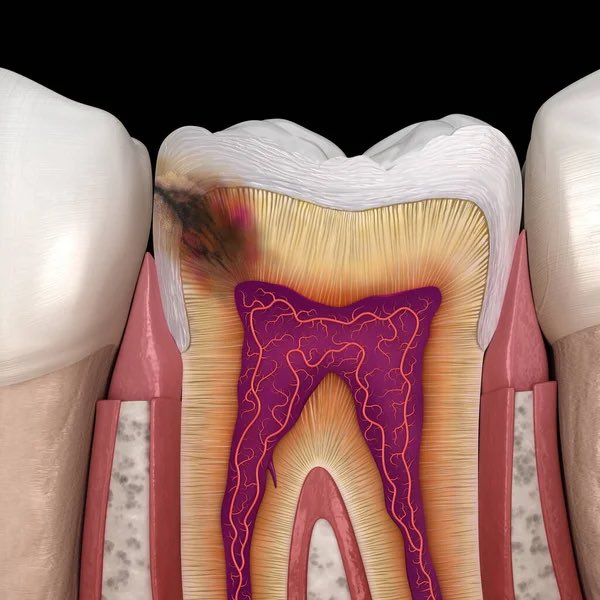

متأكد مافيك تسوسات؟ فكر شوي ترا التسوسات مو شرط تألم، لكن أذا وصلت للعصب راح تحس فيها وممكن ماتتعالج الا بعد إزالة العصب، كيف نتجنبها ؟ تابع معي👇🏼#ثريد

طريقة تجنبها سهلة جداً، في المقام الأول: الزيارة الدورية للطبيب مهمه وهي اللي تكشف هذه التسوسات بعد أخذ صور الأشعة والكشف السريري ويتم معالجتها قبل ماتتعمق وتوصل لعصب السن.